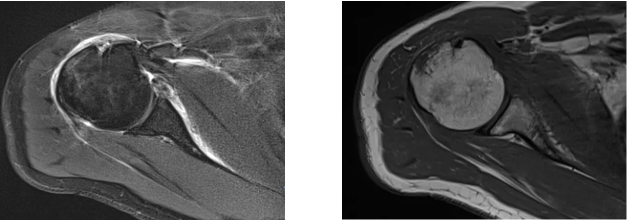

病例1

病史摘要:男性,44歲,跌傷致右肩關(guān)節(jié)疼痛數(shù)天,活動(dòng)不利。

MR圖示:右側(cè)肱骨后外上方局部骨皮質(zhì)塌陷,并鄰近皮質(zhì)下斑片狀壓脂高信號(hào)影(箭頭);前盂唇撕脫,前方見低信號(hào)游離骨片影(三角形)。